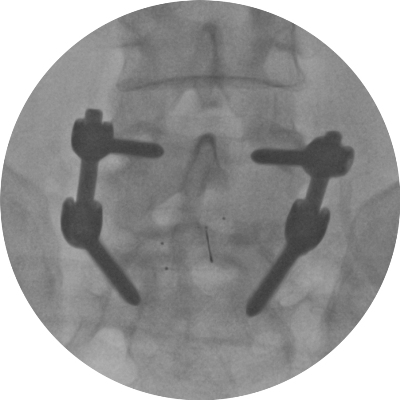

Astfel, în urma unui număr mare de investigaţii suplimentare, a fost luată decizia de a folosi un abord chirurgical numit ”fuziune intervertebrală transforaminală”. Tehnica dată este mai complicată şi mai solicitantă faţă de dotarea tehnică a blocului de operaţii şi a abilităţilor echipei chirurgicale, însă oferă un şir de avantaje pentru pacient.

Deoarece pacientul a fost operat anterior de 2 ori, utilizarea aceluiaşi coridor chirurgical tradiţional putea fi însoţită de un risc mare de leziuni a nervilor şi vaselor în canalul spinal. De aceea, a fost aleasă o cale mai puţin utilizată în practica cotidiană, dar care a fost cea mai raţională pentru pacientul dat, aşa-numitul abord paramedian transmuscular sau abordul prin spaţiul Wiltse.

Este un caz fericit pentru pacientul din Italia şi de succes pentru secţia Neurochirurgie, dar şi pentru întreaga instituţie medicală, or, astfel de intervenţii complicate au devenit posibile în Republica Moldova în urma deschiderii noului Bloc chirurgical în luna mai curent, prin intermediul căruia ţara noastră a obţinut facilităţi şi posibilităţi care au existat pînă nu demult doar în centrele medicale contemporane performante din lume. Astfel, sala de operaţii Hybrid a blocului dispune de metode de neuroimagistică intraoperatorie şi sisteme de monitoring şi neuronavigaţie, sisteme specializate de implanturi din titan şi instrumente chirurgicale, echipamente pentru disecţie osoasă. Acest complex chirurgical este completat de un departament ultradotat de anestezie şi neuroreanimare, care asigură o parcurgere perioperatorie fără complicaţii.